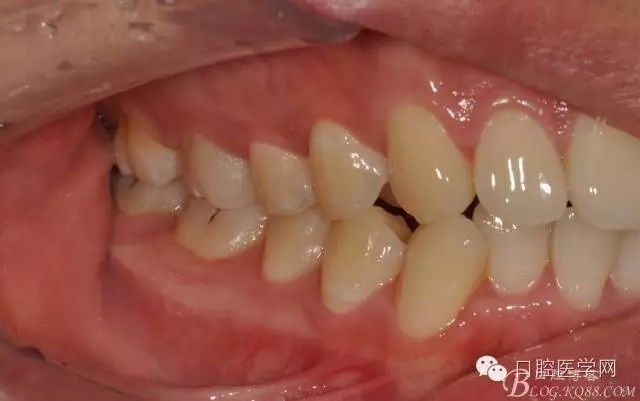

圖14 術(shù)后咬頜觀

圖15 術(shù)后連續(xù)側(cè)方位咬頜觀